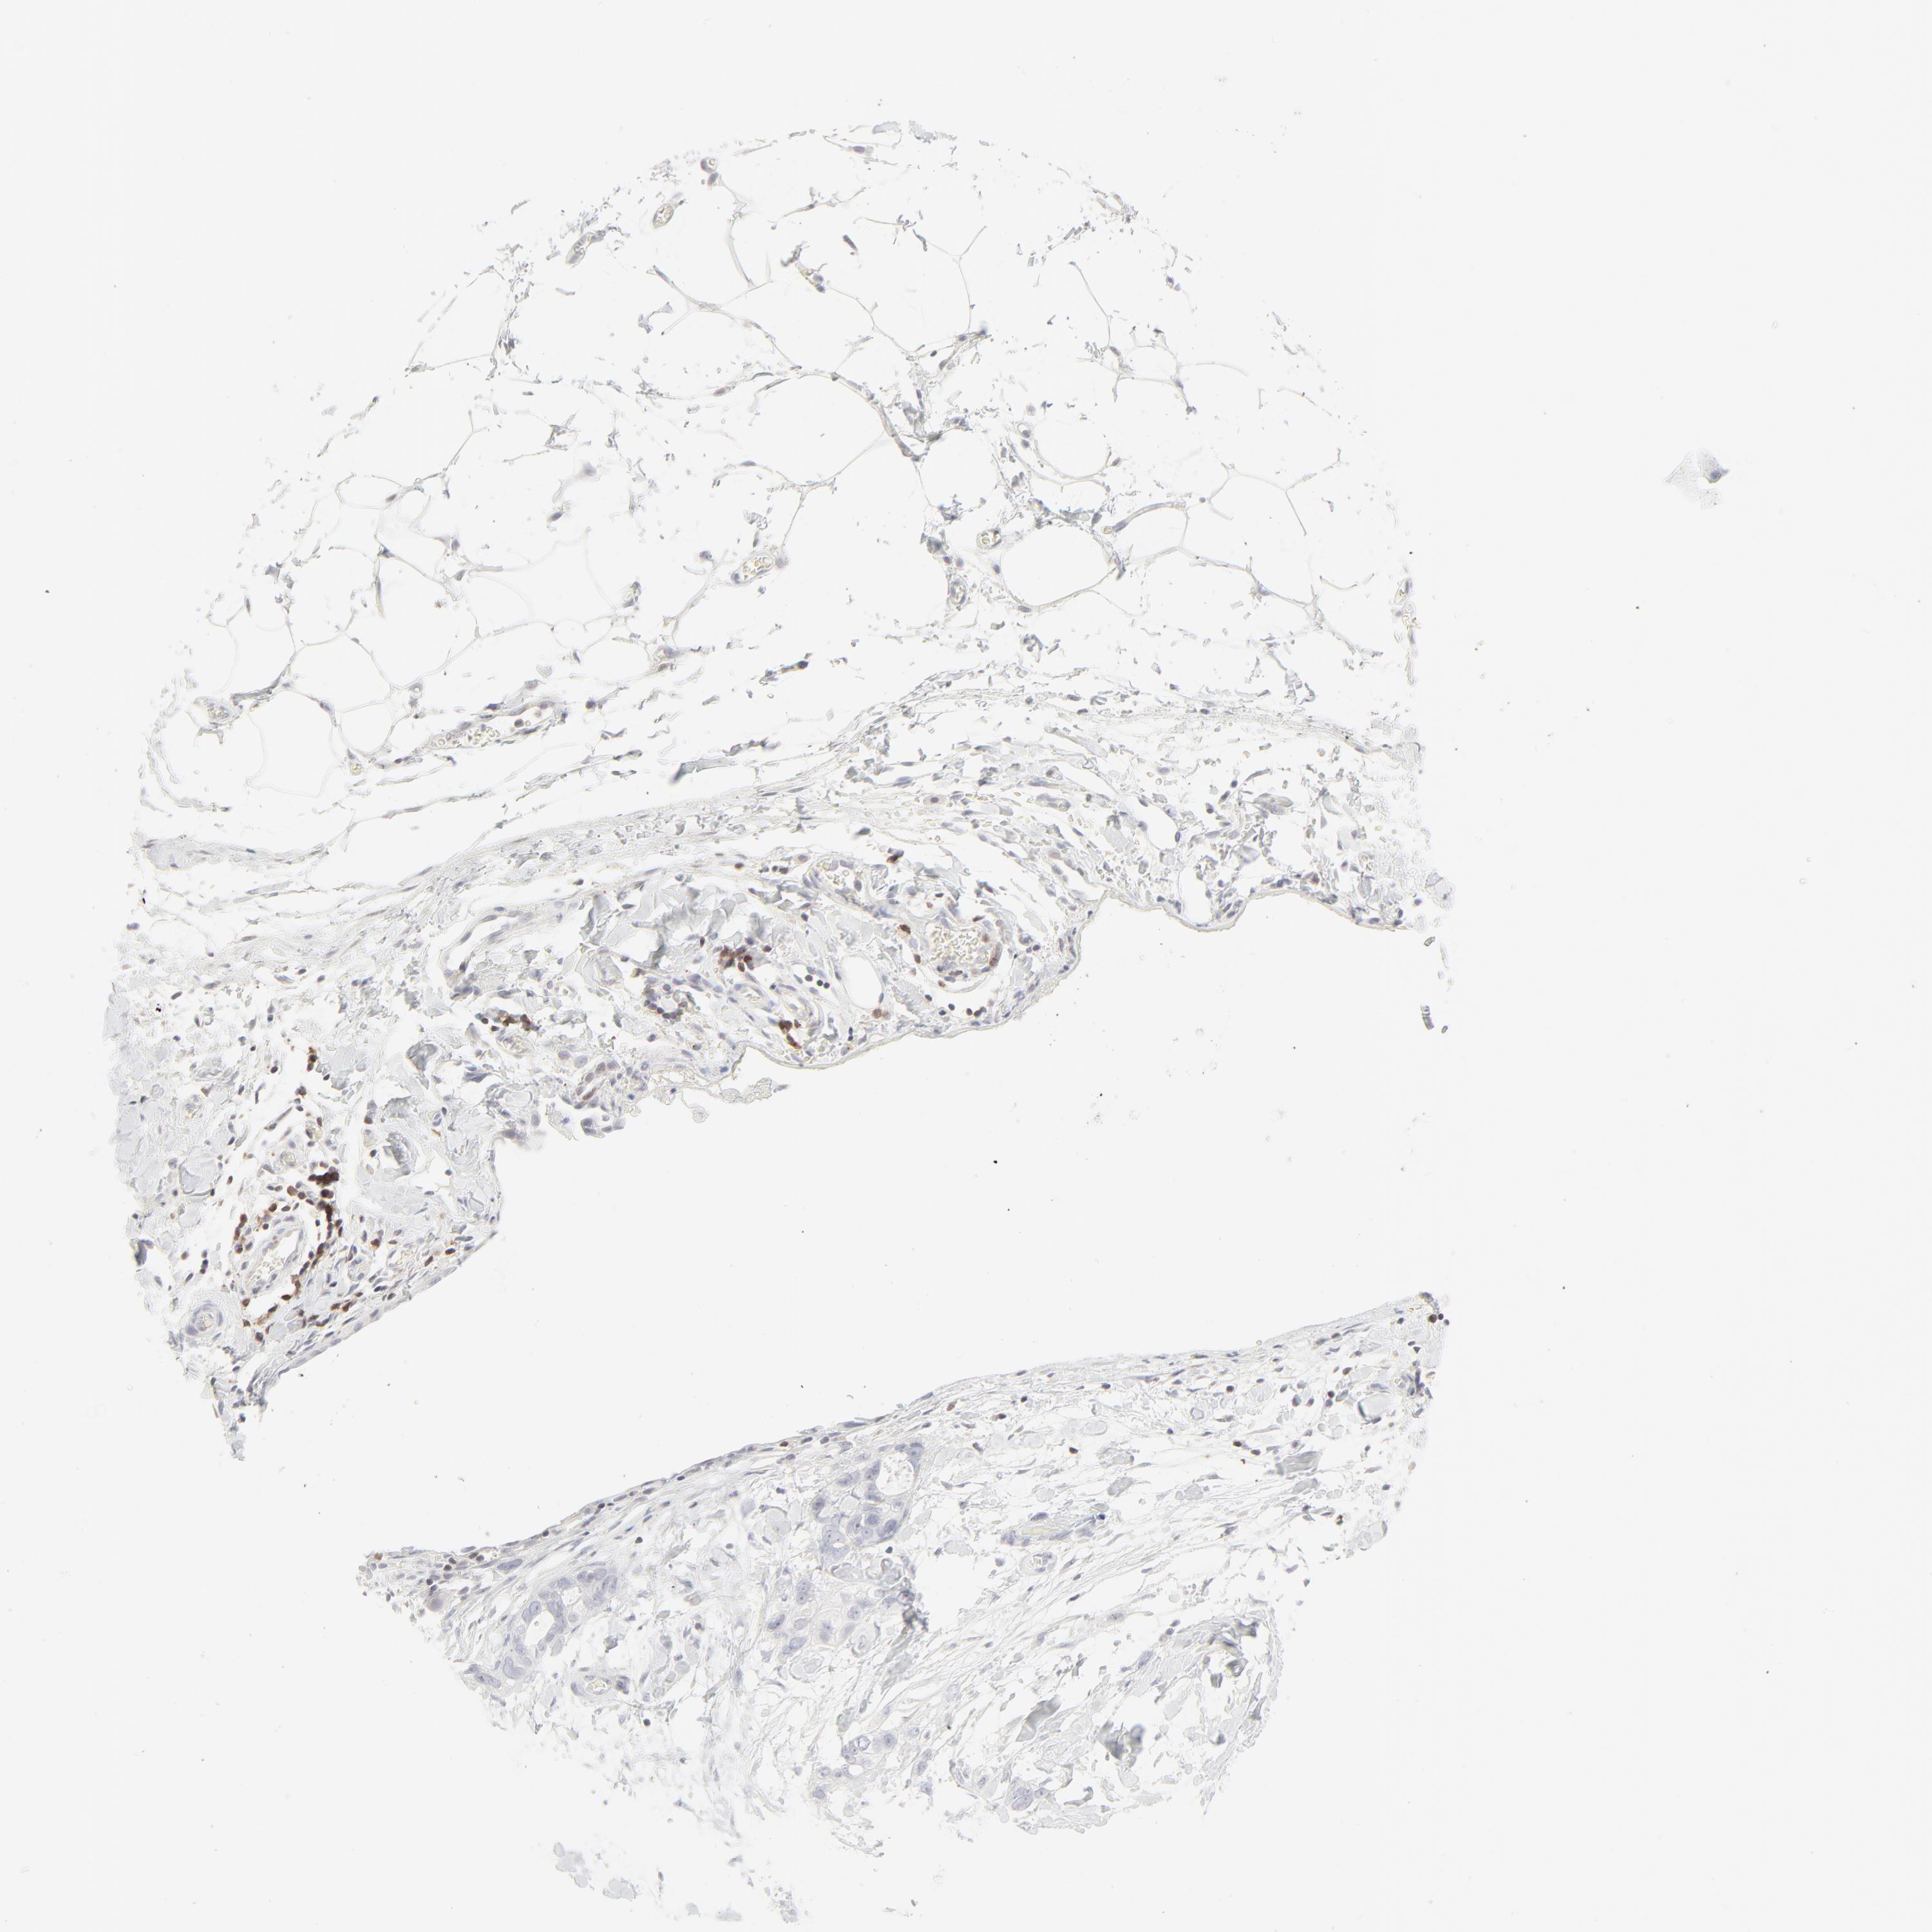

STOMACH CANCER - Protein expressioni

A mouse-over function shows sample information and annotation data. Click on an image to view it in a full screen mode. Samples can be filtered based on level of antibody staining by selecting one or several of the following categories: high, medium, low and not detected. The assay and annotation is described here.

Note that samples used for immunohistochemistry by the Human Protein Atlas do not correspond to samples in the TCGA dataset.

Antibody stainingi

Antibody staining in the annotated cell types in the current human tissue is reported as not detected, low, medium, or high, based on conventional immunohistochemistry profiling in selected tissues. This score is based on the combination of the staining intensity and fraction of stained cells.

Each image is clickable and will lead to virtual microscopy that enables deeper exploration of all samples and also displays staining intensity scores, fraction scores and subcellular localization as well as patient and tissue information for each sample.

Antibody HPA048321

Antibody CAB003843

Staining

High

Medium

Low

Not detected

Intensity

Strong

Moderate

Weak

Negative

Quantity

>75%

75%-25%

<25%

None

Location

Nuclear

Cytoplasmic/membranous

Cytoplasmic/membranous,nuclear

Adenocarcinoma, NOS